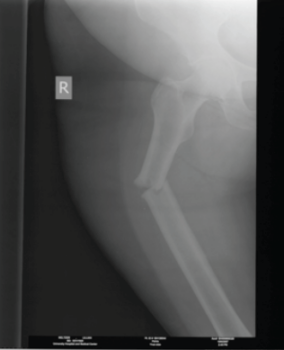

The plaintiff alleged that she called for help, but was ultimately forced to leave her walker outside the stall. When the plaintiff opened the stall door, she claimed her walker was pushed beyond her reach. The plaintiff took a step to retrieve the walker, but fell. The plaintiff was diagnosed with a femur fracture which required open reduction and internal fixation. She claimed her fall related injuries confined her to a walker for long-term, rather than short term. In addition, the plaintiff alleged that long-term use of the walker aggravated her preexisting rheumatoid arthritis to the point that a shoulder replacement was required.